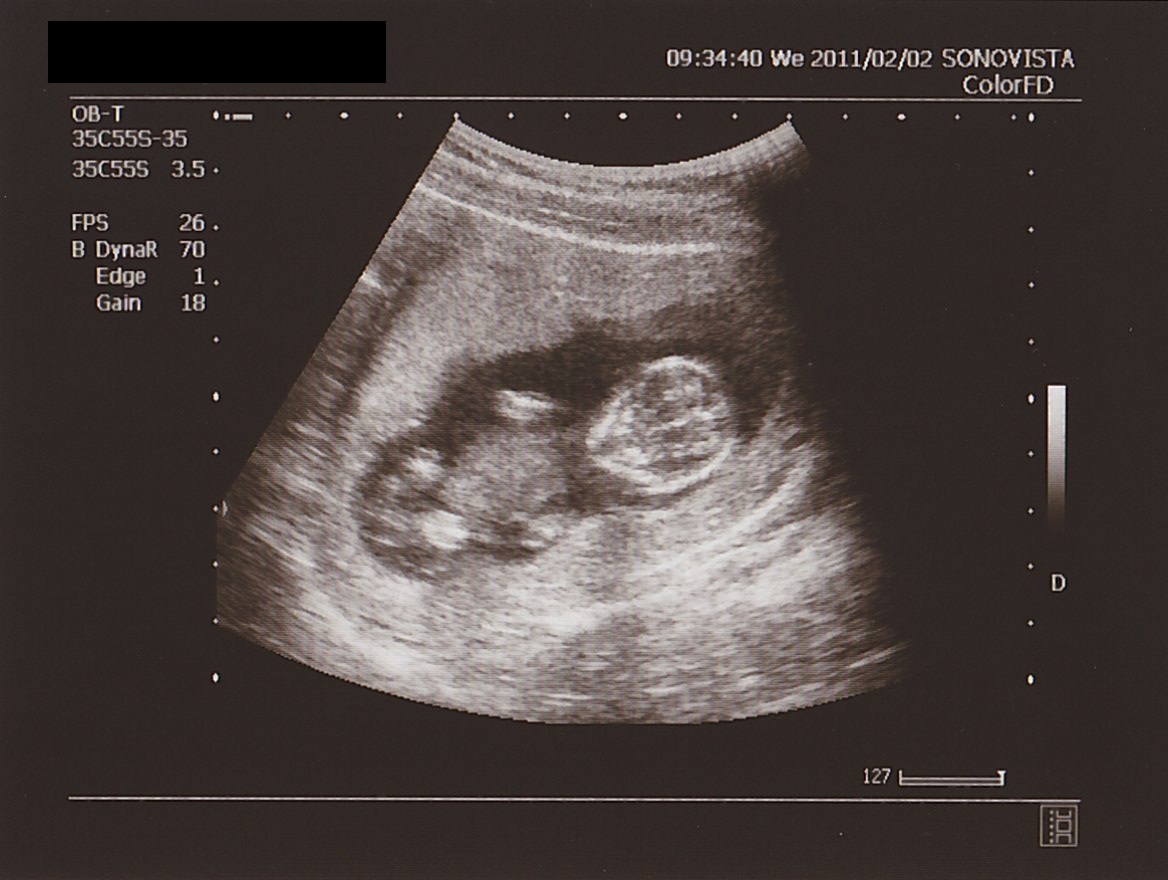

全身像は…

▲ 背骨が シッカリ 映ってる!

下を 向いている 状態。

写真上部の アーチ型が 背骨。

角度を 変えて 見たときは

肘を 曲げて

ほおづえを ついているような 格好をしていました。

ほおづえ なんて

モンちゃん おませさんー!